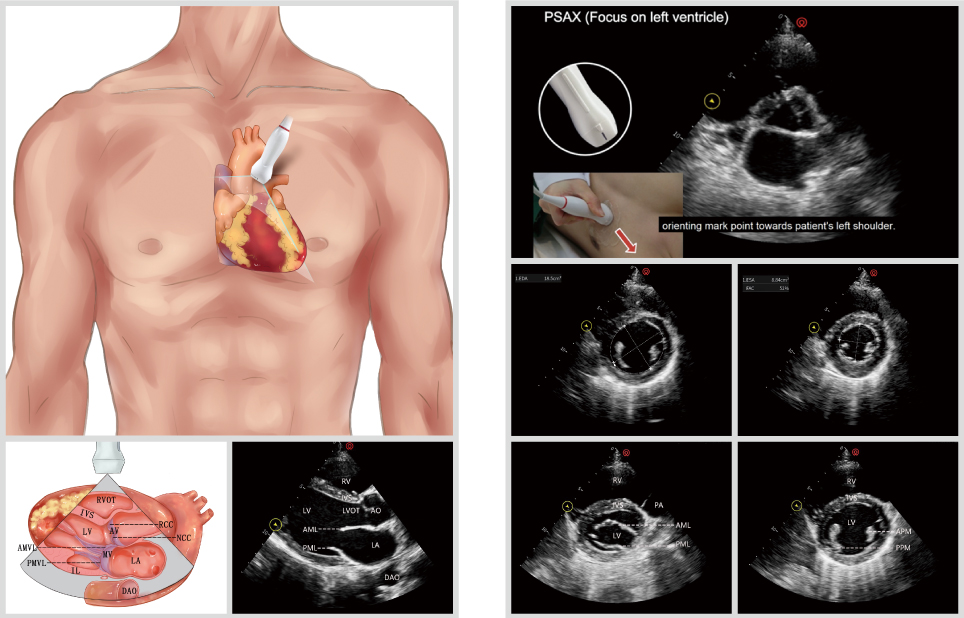

wiscan - intelligent ultrasound workflow

designed to simplify every step of scanning, wiscan delivers:

• instant access to standardized scan points

• streamlined annotation for faster reporting

• effortless review tools to minimize clinician workload

all to support rapid, confident decision-making in critical care

wilearn pro - critical care ultrasound teachingssoftware

specifically designed for critical care ultrasound education, wilearn pro offers:

• standardized scan protocols for consistent practice

• comprehensive case libraries with typical clinical scenarios

• scan-along while learning to build hands-on confidence

helping clinicians quickly master critical assessments of the heart, lungs, and abdomen with accuracy and ease